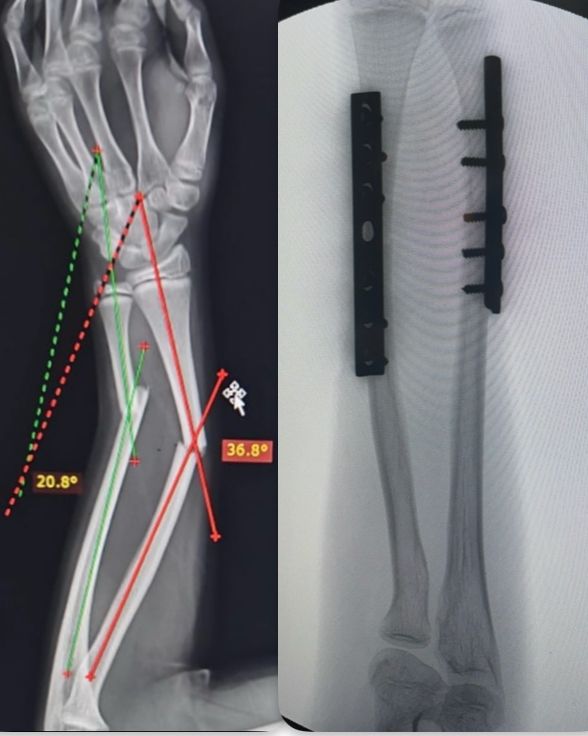

Fotos y videos